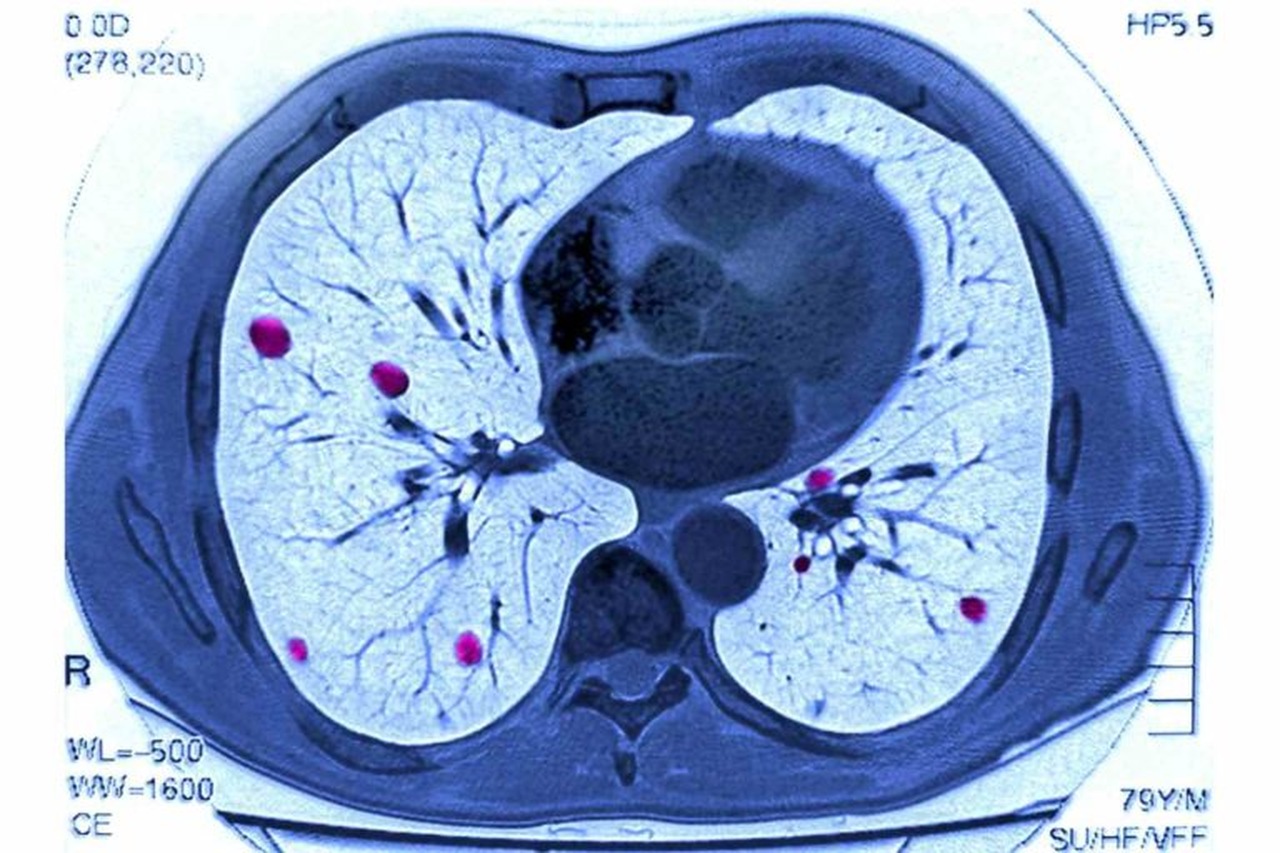

Uma conquista notável nessa área é o recente anúncio do Massachusetts Institute of Technology (MIT) e do Mass General Hospital (MGH), dos EUA, sobre o desenvolvimento de um modelo de aprendizado profundo chamado “Sybil” que pode ser usado para prever o risco de câncer de pulmão, usando dados a partir de apenas uma única tomografia computadorizada.

Os líderes do estudo afirmam que “um modelo de aprendizado profundo avaliando todos os dados volumétricos de LDCT [Low Dose Contrast CT] poderia ser construído para prever o risco individual sem a necessidade de dados demográficos ou clínicos adicionais”.

O modelo começa com um princípio básico: “As imagens LDCT contêm informações que predizem o risco futuro de câncer de pulmão além dos recursos atualmente identificáveis, como nódulos pulmonares”. Portanto, os desenvolvedores procuraram “desenvolver e validar um algoritmo de aprendizado profundo que prevê o risco futuro de câncer de pulmão em até 6 anos a partir de uma única varredura de LDCT e avaliar seu potencial impacto clínico”.

No geral, o estudo foi notavelmente bem-sucedido até agora: Sybil é capaz de prever o risco futuro de câncer de pulmão de um paciente com certa precisão, usando os dados de apenas um LDCT.